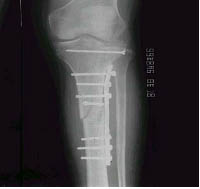

局部組織、細胞因某種致病因素的作用遭受損傷和死亡後,由鄰近健康細胞的再生來修補,以恢復組織完整性的過程。修復過程的快慢及完整與否受許多因素影響。這些因素除受損傷的組織類型外,還有致損傷因子、營養、血液供應、感染、組織缺損多少等。再生是指組織損傷後細胞分裂增生以完成修復的過程。如傷口的修復即通過血管、結締組織、上皮組織等組織的再生以完成修復的過程。此外還有人工的結構,如:人工腎、人工關節、人工瓣膜等來修補或替換損傷的組織或器官,這是一種人工的修復過程。斷肢再植就是充分利用了修復再生的規律。